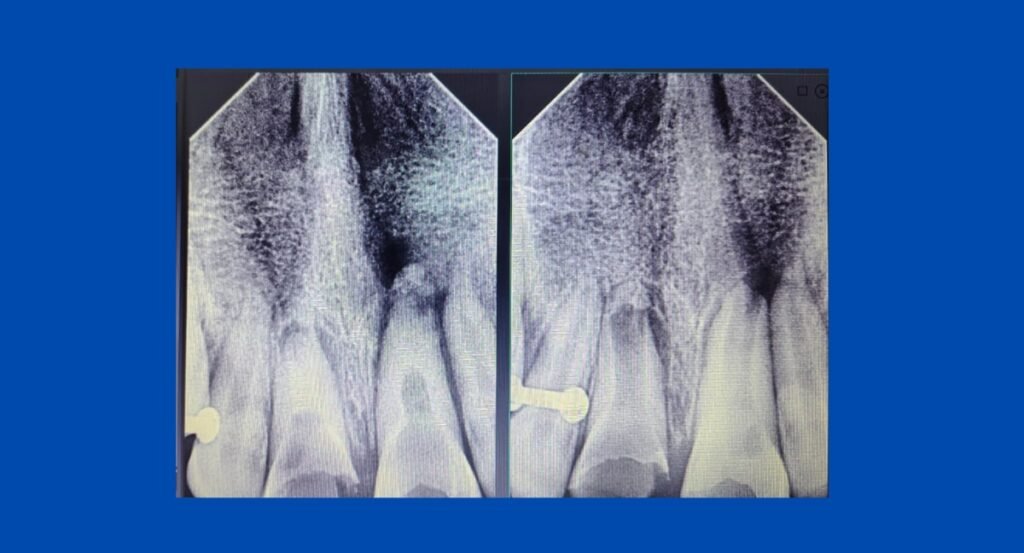

A young female patient reported with fractured and discolored upper central incisors following a road traffic accident. The injury not only compromised the health and structure of the teeth but also created esthetic concerns that deeply affected her confidence. Radiographic findings revealed pathology that required careful and staged management.

The child was treated over multiple sittings with a planned, long-term approach. The therapy was finalized with an MTA apexification procedure to achieve proper apical closure. Following this, a fiber post and core build-up was done to provide strength and reinforcement to the compromised incisors. Instead of going for a permanent crown at this stage, the teeth were restored with composite build-up and veneering, ensuring a natural esthetic outcome while preserving maximum tooth structure.

Over a span of four years, the patient was kept under close observation with regular follow-ups. Each stage of the treatment was carefully monitored, allowing healing to progress while maintaining both esthetics and function.